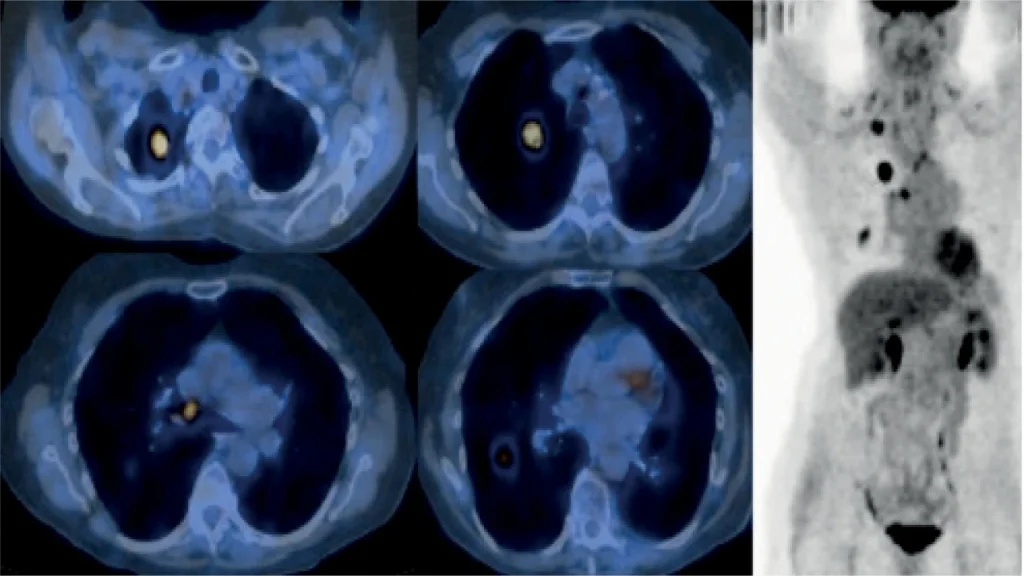

A CT pulmonary angiogram is a special type of CT scan that is used to take detailed images of the pulmonary arteries. The pulmonary arteries are the vessels that carry blood from the heart to the lungs. In order to take the images, contrast dye is injected into a vein in the arm. The dye then travels through the pulmonary arteries and makes them easier to see on the CT scan

. The CT scan is usually performed as part of an evaluation for possible Pulmonary Embolism (PE). PE is a condition where a clot has travelled from elsewhere in the body and has become lodged in one of the pulmonary arteries. A CT pulmonary angiogram can often diagnose PE even when other imaging tests are inconclusive. It is important to diagnosis PE promptly.

سیتی آنژیوگرافی ریوی نوع خاصی از سیتی اسکن است که برای گرفتن تصاویر دقیق از شریانهای ریوی استفاده میشود. شریانهای ریوی رگهایی هستند که خون را از قلب به ریهها منتقل میکنند. برای گرفتن تصاویر، رنگ کنتراست به داخل ورید بازو تزریق میشود. سپس این رنگ از طریق شریانهای ریوی عبور میکند و مشاهده آنها را در سیتی اسکن آسانتر میکند. سیتی اسکن معمولاً به عنوان بخشی از ارزیابی احتمال آمبولی ریوی (PE) انجام میشود.

آمبولی ریوی وضعیتی است که در آن لخته خون از جای دیگری از بدن حرکت کرده و در یکی از شریانهای ریوی گیر کرده است. سیتی آنژیوگرافی ریوی اغلب میتواند آمبولی ریوی را حتی زمانی که سایر آزمایشهای تصویربرداری بینتیجه هستند، تشخیص دهد. تشخیص سریع آمبولی ریوی بسیار مهم است.